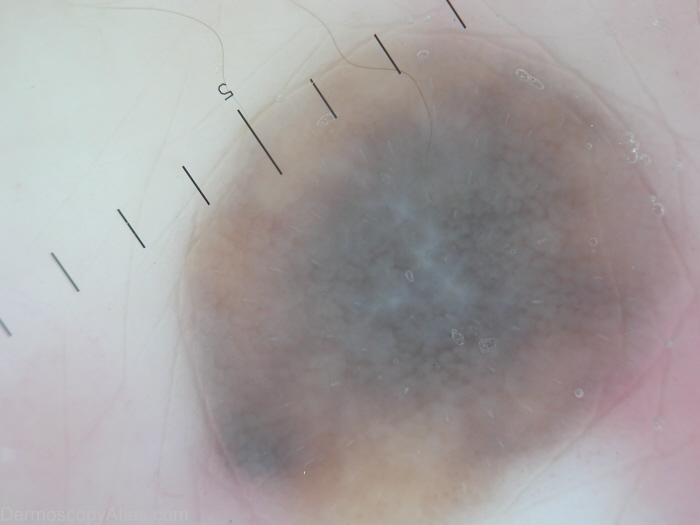

Diagnosis - Nevus blue fibrosing

Diagnosis: Nevus blue fibrosing